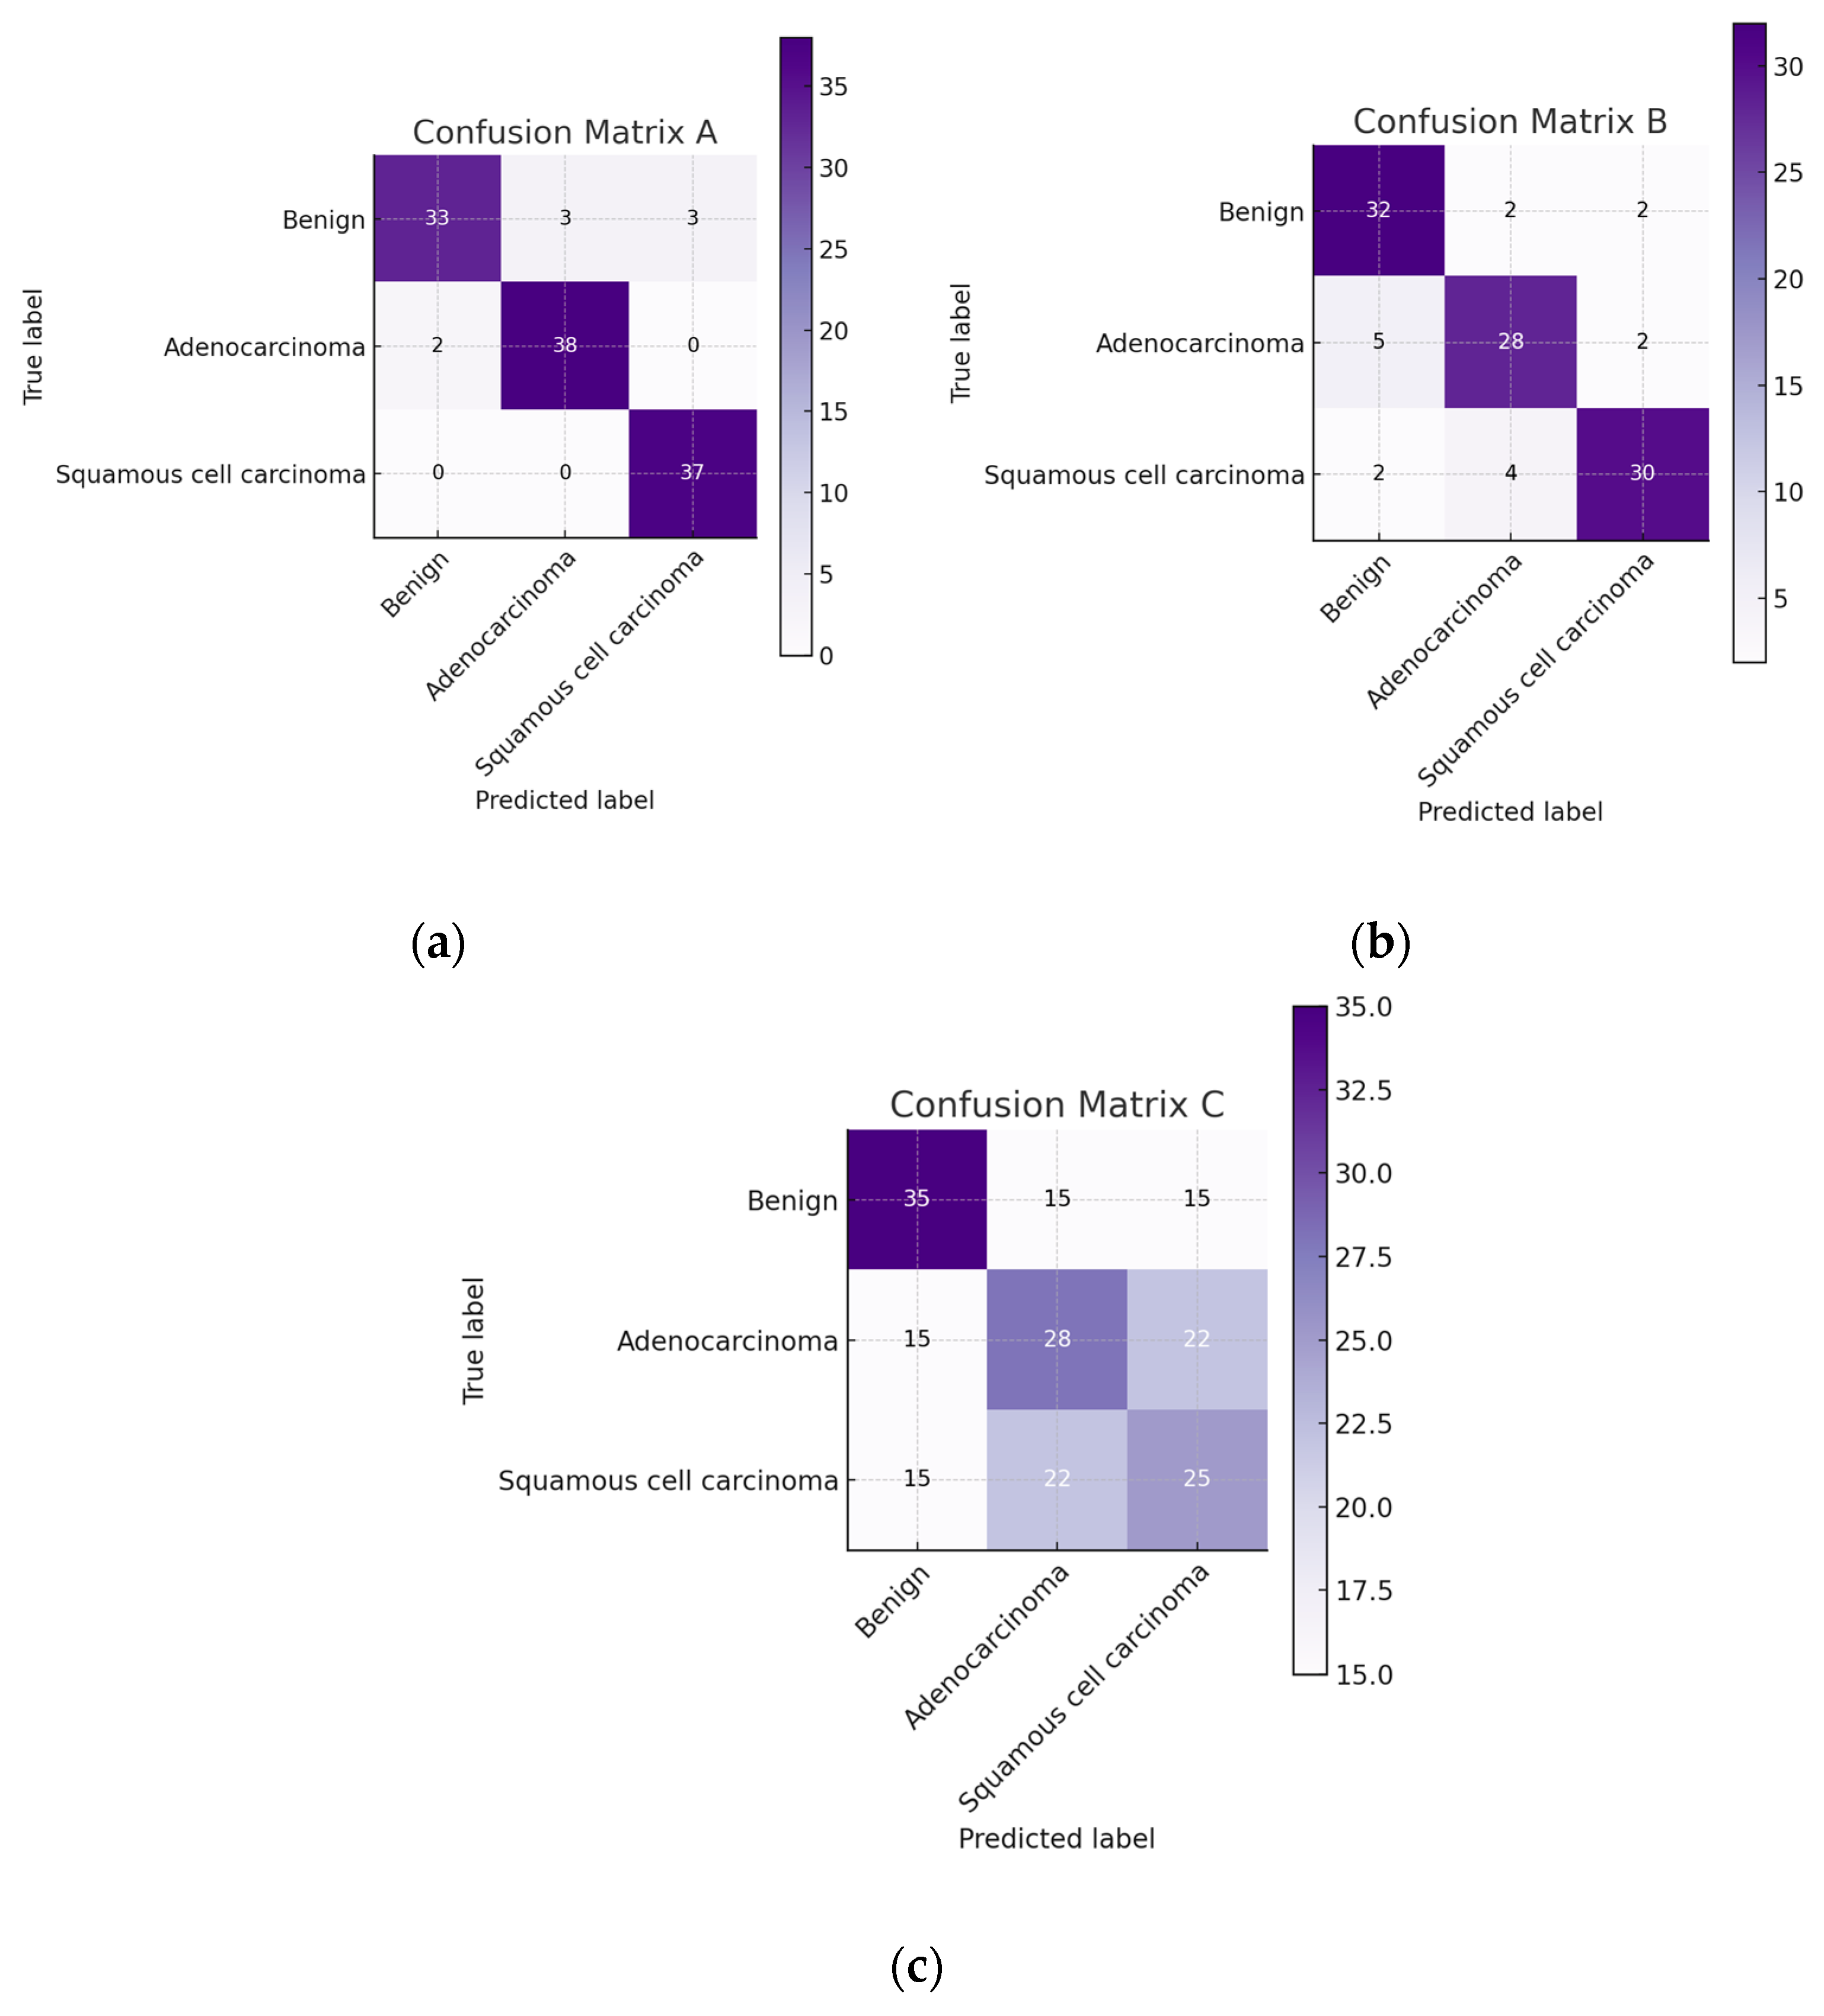

4.2. Histopathological Images

First, we present the results associated with cancer detection for histopathological images. In the context of evaluating the performance of classification models within machine learning, the confusion matrix stands out as a pivotal tool. This matrix provides a detailed breakdown of the predictions made by a model, allowing for a nuanced assessment of its performance in terms of accurately predicting different classes. The confusion matrix is structured as a table, categorizing predictions into four fundamental types: True Positives (TP), True Negatives (TN), False Positives (FP), and False Negatives (FN). TPs and TNs represent instances where the model has correctly predicted the positive and negative classes, respectively. By contrast, FPs and FNs reflect the errors in prediction, where the model incorrectly identifies the positive and negative classes.

Derived from the confusion matrix, several key performance metrics that offer insights into different aspects of the model’s predictive accuracy are accuracy, precision, recall, and F1 score. These metrics, derived from the confusion matrix, are instrumental in comprehensively understanding the performance of a classification model. They highlight not only the model’s accuracy but also the nature and extent of any prediction errors, thereby guiding further model refinement and optimization.

We had 750 images in total representing three different classes and an even distribution of 250 images for each class. We reserved 15% of the data for validation, and the results presented are based on this validation data performance.

Figure 5 presents the confusion matrix for ATT-DenseNet implementation along with two other baselines, namely AlexNet and SqueezeNet.

As we can see from the presented confusion matrices in

Figure 5, very few samples have been misclassified by the DenseNet compared to the baselines.

Figure 6 provides a figure showing the performance of DenseNet against AlexNet and SqueezeNet in terms of accuracy, precision, recall, and F1 score. For all the performance metrics, DenseNet performs better. DenseNet’s architecture allows for each layer to have direct access to the gradients from the loss function and the original input signal, leading to more efficient training and feature reuse. This is particularly useful in histopathological image analysis, where subtle features and patterns are crucial for accurate classification. Furthermore, in DenseNet, each layer receives a “collective knowledge” from all preceding layers, which improves the flow of gradients throughout the network. This leads to better learning and performance, as each layer can learn more complex features based on all previous layers. To further improve the performance, as presented in

Section 3, we adopt ATT-DenseNet, which is our proposed method. We achieved the following performance (

Figure 7), which surpasses the traditional DenseNet, AlexNet and SqueezeNet.